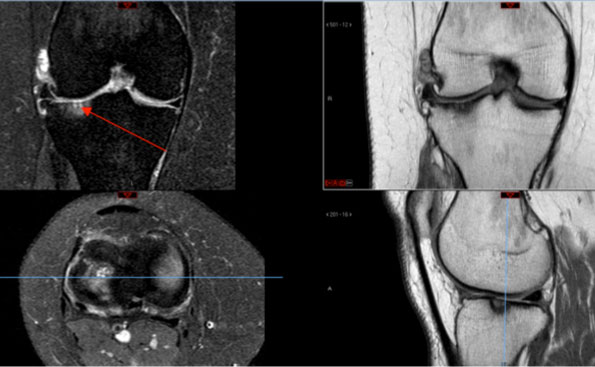

Distale Femurosteotomie (Oberschenkel), Tomofix, Depuy Synthes rechts

Beispiel einer distalen Femurosteotomie mit Tomofix-Plattensystem. Die oberen Bilder entsprechen der MRI-Bildgebung, im oberen linken Bild ist durch den roten Pfeil ein Knochenödem am Unterschenkel markiert. In der Ganzbeinaufnahme ist zu sehen, wie aus dem X-Bein ein O-Bein wurde. Die mechanische Beinachse (rot) wurde vom Aussengelenk in das Innengelenk des Knies verlagert.